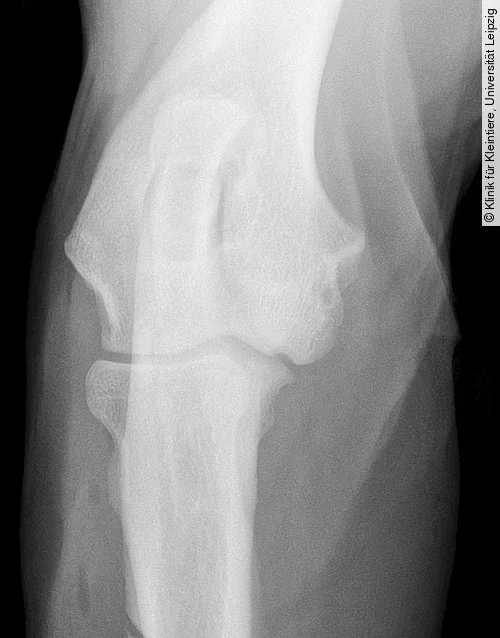

Projektionsradiografie Kniegelenk

Für die Darstellung der OCD am lateralen und medialen Condylus femoris wird eine mediolaterale und eine kraniokaudale oder kaudokraniale Röntgenaufnahme benötigt. Obwohl die mediolaterale Aufnahme häufig schon pathognomonische Anzeichen der OCD zeigt, ist eine kraniokaudale oder kaudokraniale Projektion erforderlich, um festzustellen, welcher Kondylus betroffen ist [4].

Die Röntgenbilder können Veränderungen wie eine Abflachung der Gelenkoberfläche an einem der beiden Femurkondylen (meist Medialfläche lateraler Kondylus), einen konkaven Defekt am subchondralen Knochen (mit oder ohne angrenzende Sklerose) oder selten mineralisierte Knorpelschuppen zeigen (Abb. [ 6 ], Abb. [ 7 ]).

Differenzialdiagnostisch kann es zu einer Verwechslung der normalen Fossa extensoria (Ursprung M. extensor digitorum longus) mit einer OCD-Läsion kommen. Die Fossa resultiert aber im Gegensatz zur OCD-Läsion nicht in einem Defekt der Gelenkfläche (kraniokaudale Projektion) und ist auf der mediolateralen Aufnahme deutlich weiter kranial und proximal lokalisiert (Abb. [ 6 ]) [4], [22].

Zur besseren Diagnosesicherung, vor allem bei Verdacht auf kleinere Läsionen im Bereich des Kniegelenks, bietet sich die Computertomografie an (Abb. [ 7 ], Abb. [ 8 ]) [18].